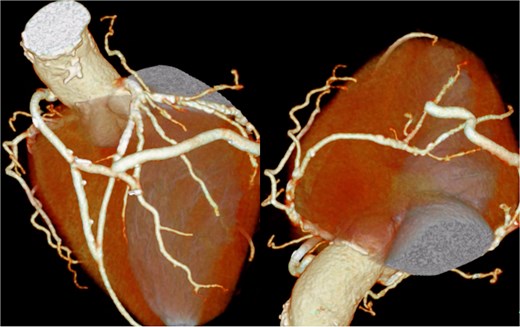

The patient underwent median sternotomy, and the non-touch SVG was harvested from the right leg. Cardiopulmonary bypass via the area around the origin of the brachiocephalic artery and the right atrium was established using the Seldinger technique. The proximal anastomosis of the SVG was performed on the right lateral wall of the ascending aorta using the Heartstring III Proximal Seal System (Maquet Cardiovascular LLC, Getinge AB, Rastatt, Germany), and exposure was facilitated by a stabilizer. The SVG was anastomosed to the left anterior descending artery, and another SVG segment was joined end-to-side to construct a T-composite graft. Then, the T-composite SVG was sequentially anastomosed to the diagonal branch, obtuse marginal branch, atrioventricular branch, and posterior descending branch. However, torsion caused narrowing of the SVG just distal to the diagonal anastomosis; therefore, a clip was applied, and the SVG was divided at that site. Then, the distal segment of the SVG was re-anastomosed end-to-side to the SVG that had been anastomosed to the diagonal branch (Fig. 4) (Video 1). After completion of the anastomoses, the patient was weaned from cardiopulmonary bypass, and surgery was completed. The postoperative course was uneventful, and the patient was transferred to another hospital for rehabilitation on postoperative day 28. At ~2 years after surgery, the patient was free from heart failure recurrence. Because symptoms of lower limb ischemia did not develop, revascularization of the lower limbs was not performed.

Postoperative coronary 3D CT angiography. Postoperative cardiac 3D CT image showing the final graft configuration. A SVG was anastomosed to the left anterior descending artery. Another SVG segment was joined end-to-side to construct a T-composite graft. This composite SVG was sequentially anastomosed to the diagonal branch, obtuse marginal branch, atrioventricular branch, and posterior descending branch. After revision because of torsion just distal to the diagonal anastomosis, the distal SVG segment was re-anastomosed end-to-side to the SVG connected to the diagonal branch, resulting in the final graft arrangement demonstrated in this image.